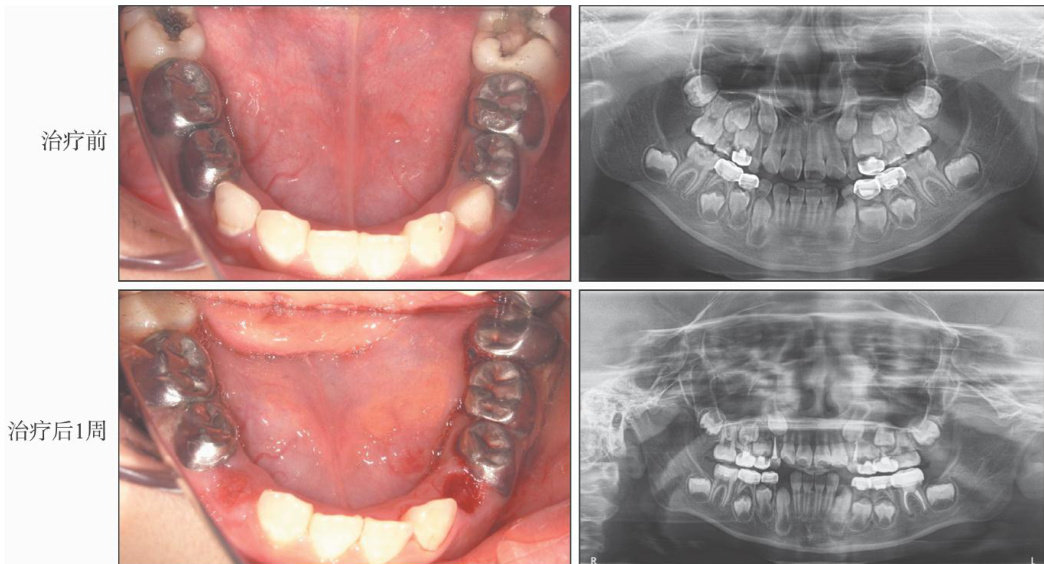

[摘要]年轻恒牙是指已萌出但在形态和结构上尚未形成和成熟的恒牙,其疾病的发病情况和治疗方法有其自身特点。由于特殊卫生保健需求儿童不能配合常规的牙科门诊治疗,大多选择在全身麻醉下进行。随着社会发展,儿童牙科全身麻醉技术的需求越来越大,本文探讨全身麻醉下年轻恒牙疾病的治疗策略,包括龋病、牙髓病根尖周疾病等的诊断、治疗原则及治疗方法等。(剩余13080字)